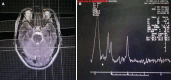

Methods: A retrospective analysis of 62 hospitalized patients clinical diagnosed with AD who were admitted to our hospital from November 2015 to November 2020. Collect cognitive dysfunction performance characteristics, laboratory test data and neuroimaging data from medical records within 24 h of admission, including Mini Mental State Examination Scale score, drawing clock test, blood T lymphocyte subsets, and neutrophils and lymphocyte ratio (NLR), disturbance of consciousness, extrapyramidal symptoms, electroencephalogram (EEG) and head nucleus magnetic spectroscopy (MRS) and other data. Multivariate logistic regression analysis was used to determine independent prognostic factors. the modified Rankin scale (mRS) was used to determine whether the prognosis was good. The correlation between drug treatment and prognostic mRS score was tested by the rank sum test.

Results: Univariate analysis showed that abnormal cellular immune function, extrapyramidal symptoms, obvious disturbance of consciousness, abnormal EEG, increased NLR, abnormal MRS, and complicated pneumonia were related to the poor prognosis of AD patients. Multivariate logistic regression analysis showed that the decrease in the proportion of T lymphocytes in the blood after abnormal cellular immune function (odd ratio: 2.078, 95% confidence interval: 1.156-3.986, P < 0.05) was an independent risk factor for predicting the poor prognosis of AD. The number of days of donepezil treatment to improve cognitive function was negatively correlated with mRS score (r = 0.578, P < 0.05).